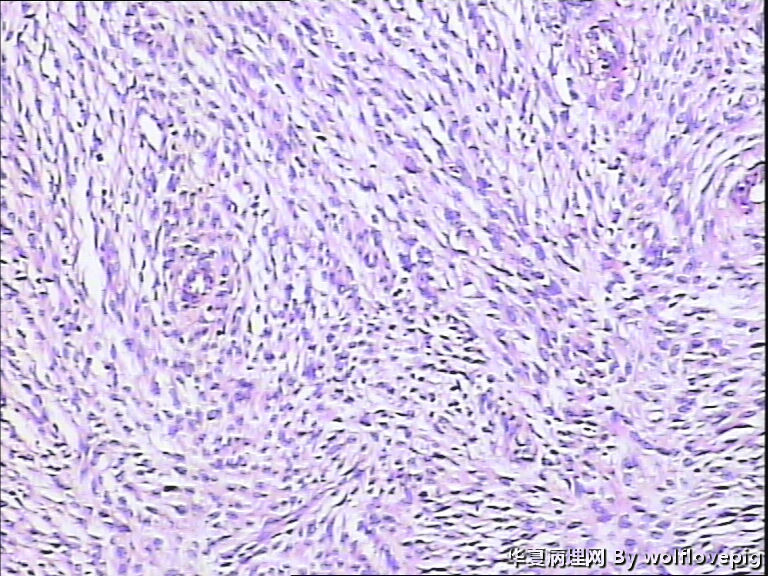

37y,肌壁间可见多个小结节0.2~0.8cm。